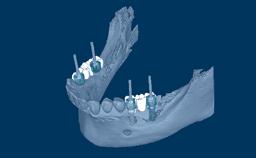

Desde a introdução dos implantes dentários, a pesquisa demonstrou que a eficácia clínica das próteses implantossuportadas é igual ou superior ao desempenho da terapia protética convencional fixa ou removível. O sucesso cientificamente documentado dos implantes levou ao desenvolvimento de muitos desenhos diferentes de implantes, materiais, tecnologias de superfície e métodos cirúrgicos. Numerosas empresas fabricam e comercializam sistemas de implantes, e a maioria desses sistemas inclui implantes de mais de um desenho. Atualmente, existem mais de 2.000 desenhos de implantes disponíveis em todo o mundo. Além disso, alguns desses sistemas incluem componentes protéticos projetados para serem compatíveis apenas com implantes do mesmo fabricante. Portanto, a escolha de um sistema de implante requer uma consideração cuidadosa. Este módulo irá rever os vários fatores que influenciam o clínico a selecionar o sistema mais adequado para seus pacientes.